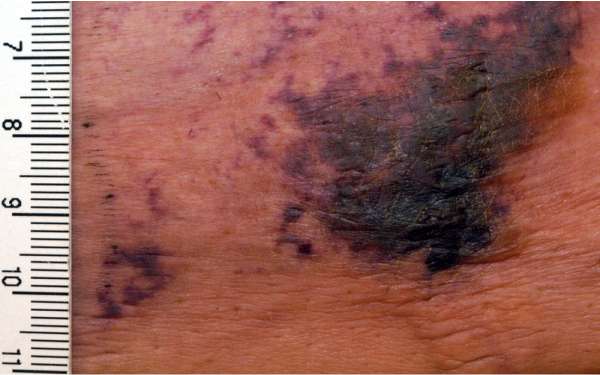

- The lesion has a large purple web-like pattern on the skin

- Deep and very painful lumps that ulcerate creating open sores with brownish-black crusts that fail to heal